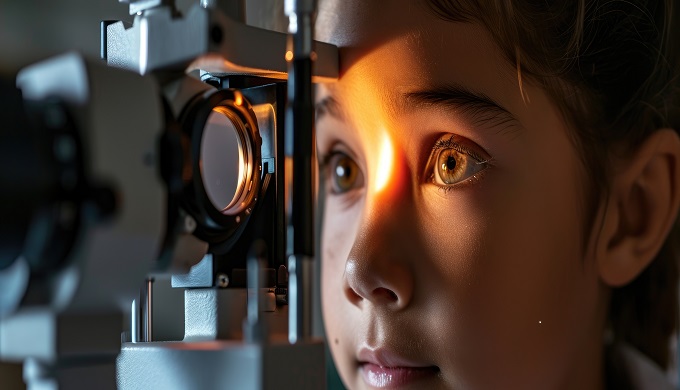

European retinoblastoma report shows stabilised incidence, high 5-year survival

The incidence of retinoblastoma in children in Europe stabilised between 2000 and 2013, say EUROCARE-6 Working Group investigators who report high 5-year survival rates in this population.